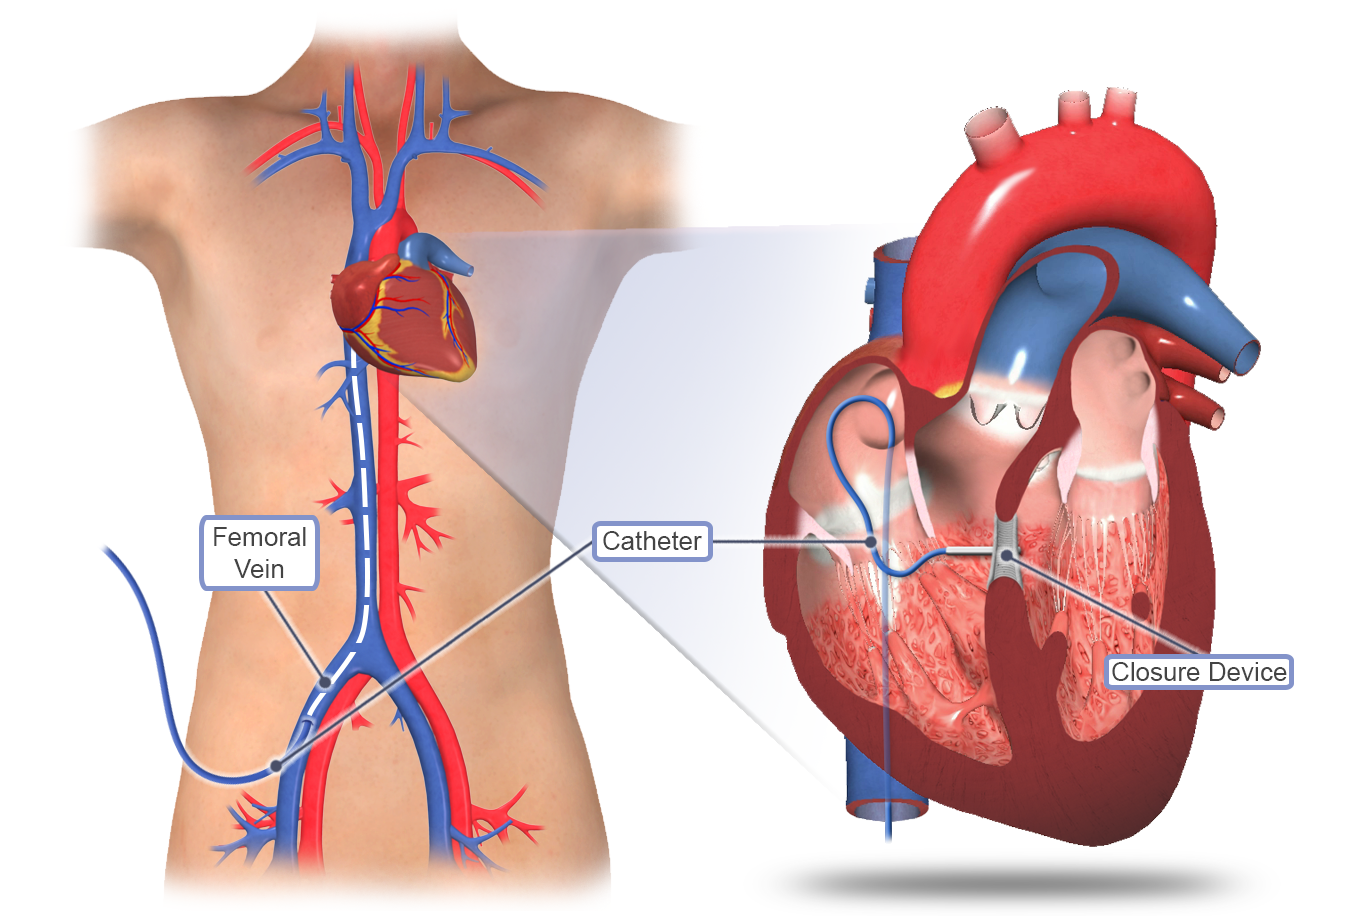

Value added benefits of the ASD Surgical Closure Open Surgery:

Ø Doctor consultation charges

Ø Lab tests and diagnostic charges

Ø Room charges inside hospital during the procedure

Ø Surgeon Fee

Ø Nursing charges

Ø Hospital surgery suite charges

Ø Anesthesia charges

Ø Routine medicines and routine consumables (bandages, dressings etc.)

Ø Food and Beverages inside hospital stay for patient and one attendant.

Overview

Package includes:

Days in hospital : 7 to 8 Day (For patient and one attendant)

Days in hotel : 14 Days (For patient and one attendant)

Room type in hospital : Shared

Room type in hotel : Private

Hotel category: Standard

Value added benefits of the VSD Surgical Closure Open Surgery:

Ø Doctor consultation charges

Ø Lab tests and diagnostic charges

Ø Room charges inside hospital during the procedure

Ø Surgeon Fee

Ø Nursing charges

Ø Hospital surgery suite charges

Ø Anesthesia charges

Ø Routine medicines and routine consumables (bandages, dressings etc.)

Ø Food and Beverages inside hospital stay for patient and one attendant.

Extra benefits: